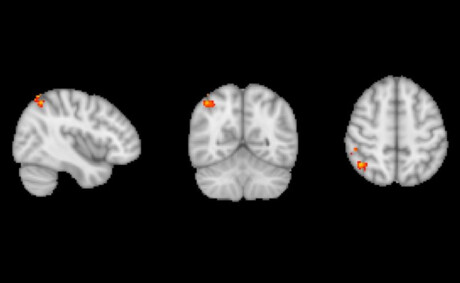

The researchers found that, compared with those taking the placebo, the volunteers taking prucalopride were both significantly better at the memory test after the scan, and also had fMRI scans indicating enhanced activity in brain areas related to cognition. The increased activity was in areas associated with memory, such as the hippocampus and the right angular gyrus. The team’s results were presented at the 34th ECNP Congress and published in the journal Translational Psychiatry.